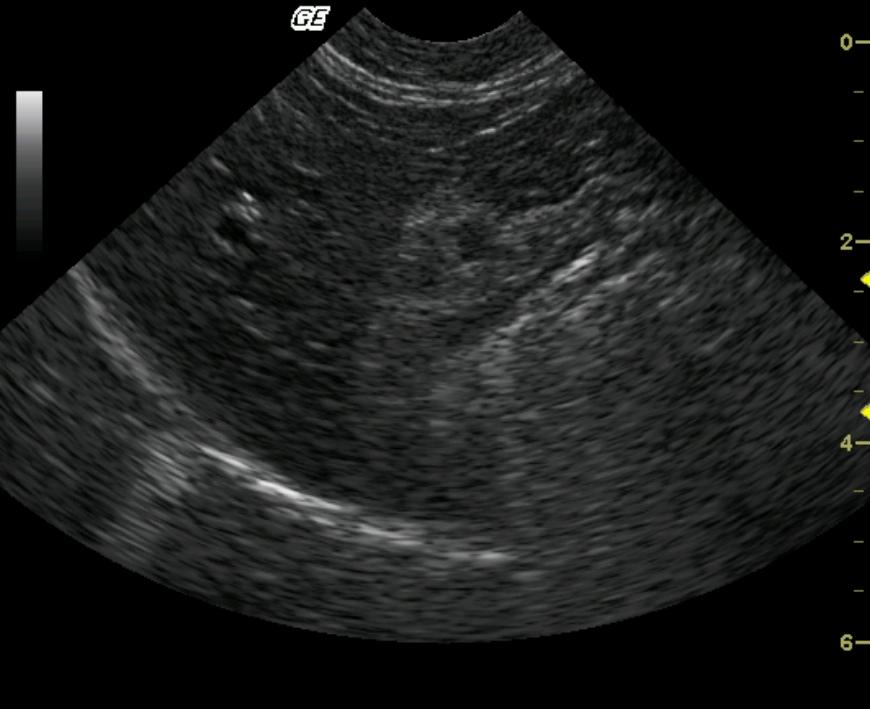

A 7-year-old F intact DSH was presented for the evaluation of dyspnea. The physical exam revealed muffled heart sounds and a thoracocentesis was performed bilaterally. One hundred milliliters (ml) of fluid was obtained from the right hemithorax and 35 ml from the left. Fluid analysis revealed cellularity to be moderate to high and RBC 100,000. Blood chemistry was performed and revealed the following abnormalities: CK 1359, albumin 3.4 g/l, direct bilirubin 0.2, and glucose 158 mg/dl.